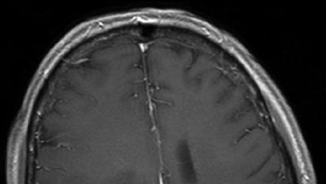

Brain Cancer Topples Leukemia as Primary Cause of Cancer Death among Children

Brain cancer is now the leading cause of cancer death in children, taking the place of leukemia, according to a new report.